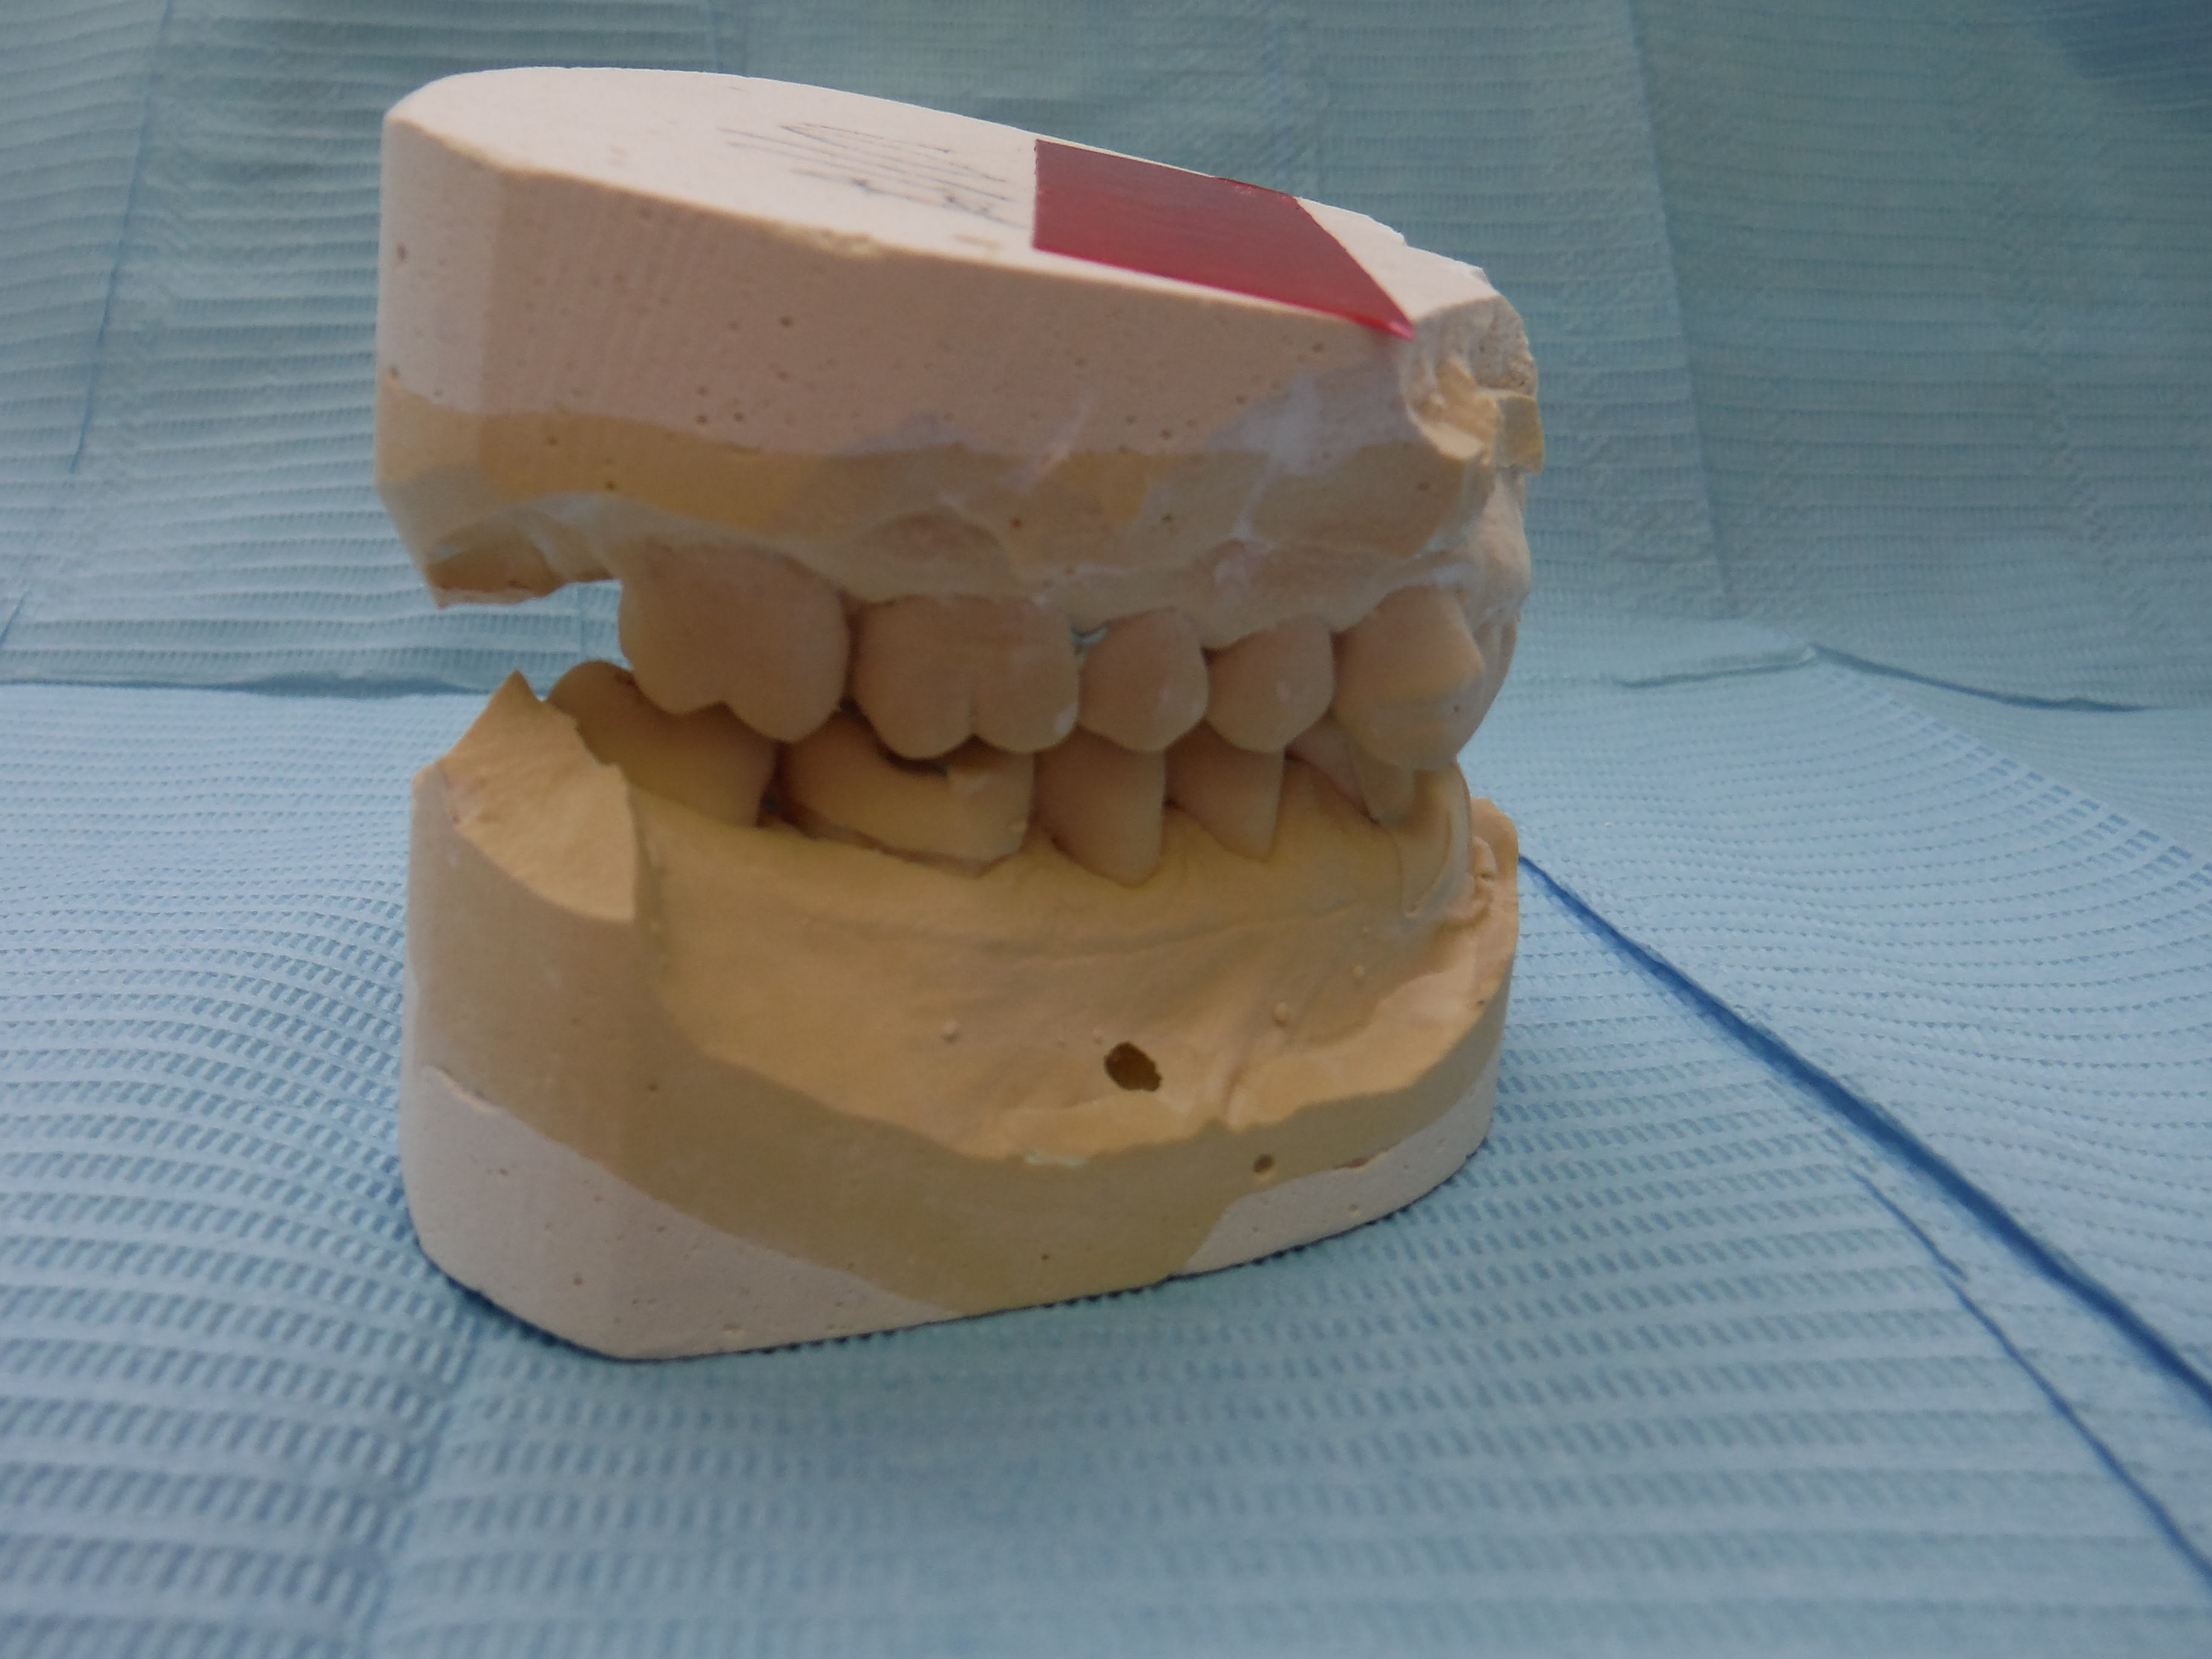

Les modèles arriverons dans qq jours.

Nivellement + contact incisif excessif probable .

Ce n est que musculaire pour l instant . Ensuite a force de serrer , les dents du haut vont se palatiniser avec de zolies mylolyses . .

sans commentaire.

Ah si! 64 ans... et 41, 31 HS...